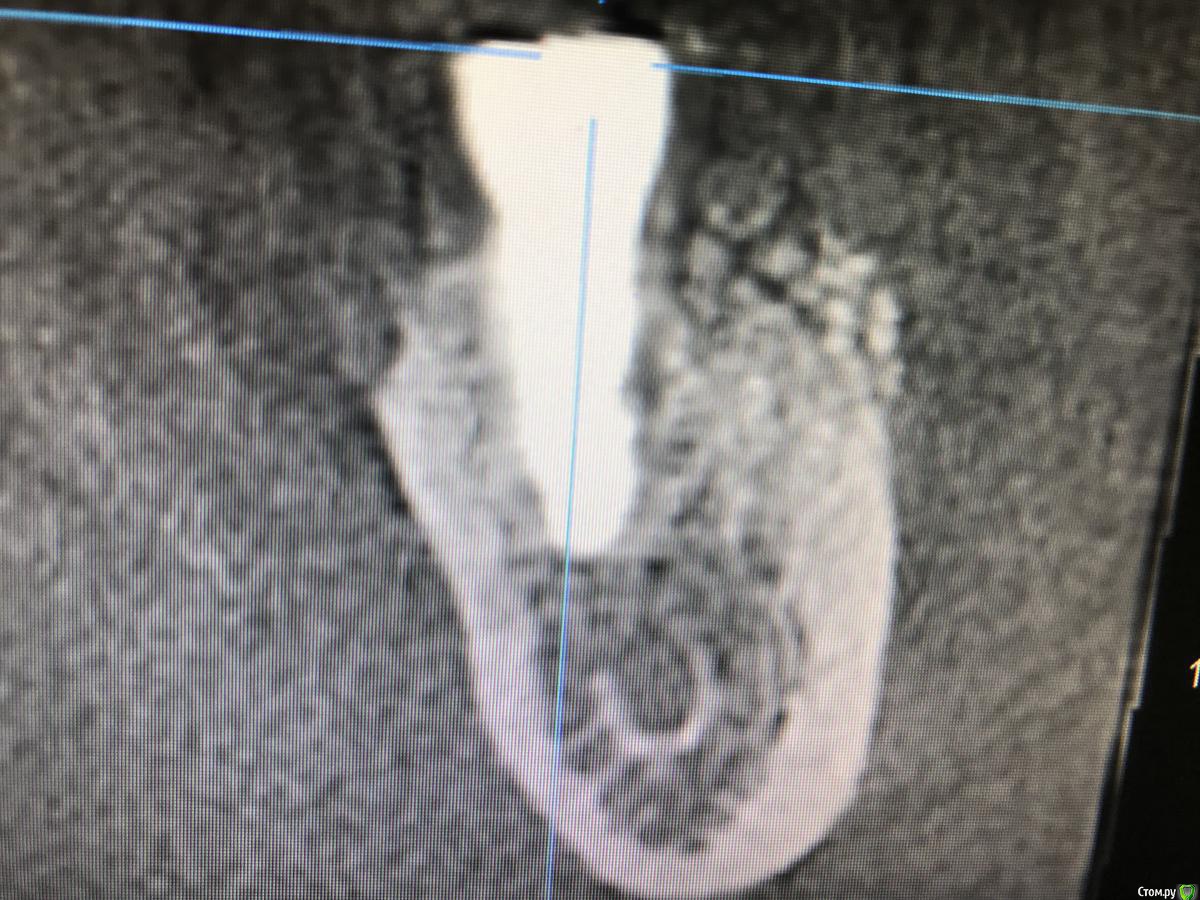

колесников Опубликовано 15 марта, 2019 Автор Поделиться Опубликовано 15 марта, 2019 Вот так выглядит интегрированый графт и соответственно не созревший. Время ожидания примерно равнозначное Ссылка на комментарий

колесников Опубликовано 16 марта, 2019 Автор Поделиться Опубликовано 16 марта, 2019 (изменено) Ну как бы тут все очевидно. Слева стала костью,справа нет. Но должен вам отметить,что даже в случае неудачи (как кажется)потери нет. Задача стояла не увеличить объём для имплантации или укрыть Имплант,а снять напряжение с вершины гребня и дать созреть десне. Имплант в нативной кости,он интегрирован,десна успела созреть за это время,возможно будет не так объёмно как хотелось бы,но у меня в запасе этап раскрытия ,фдм зарос ,есть с чем поработать. Все что не интегрировалось ,лизируется самостоятельно,выскребать ничего не нужно,ещё подождать. Изменено 16 марта, 2019 пользователем колесников Ссылка на комментарий